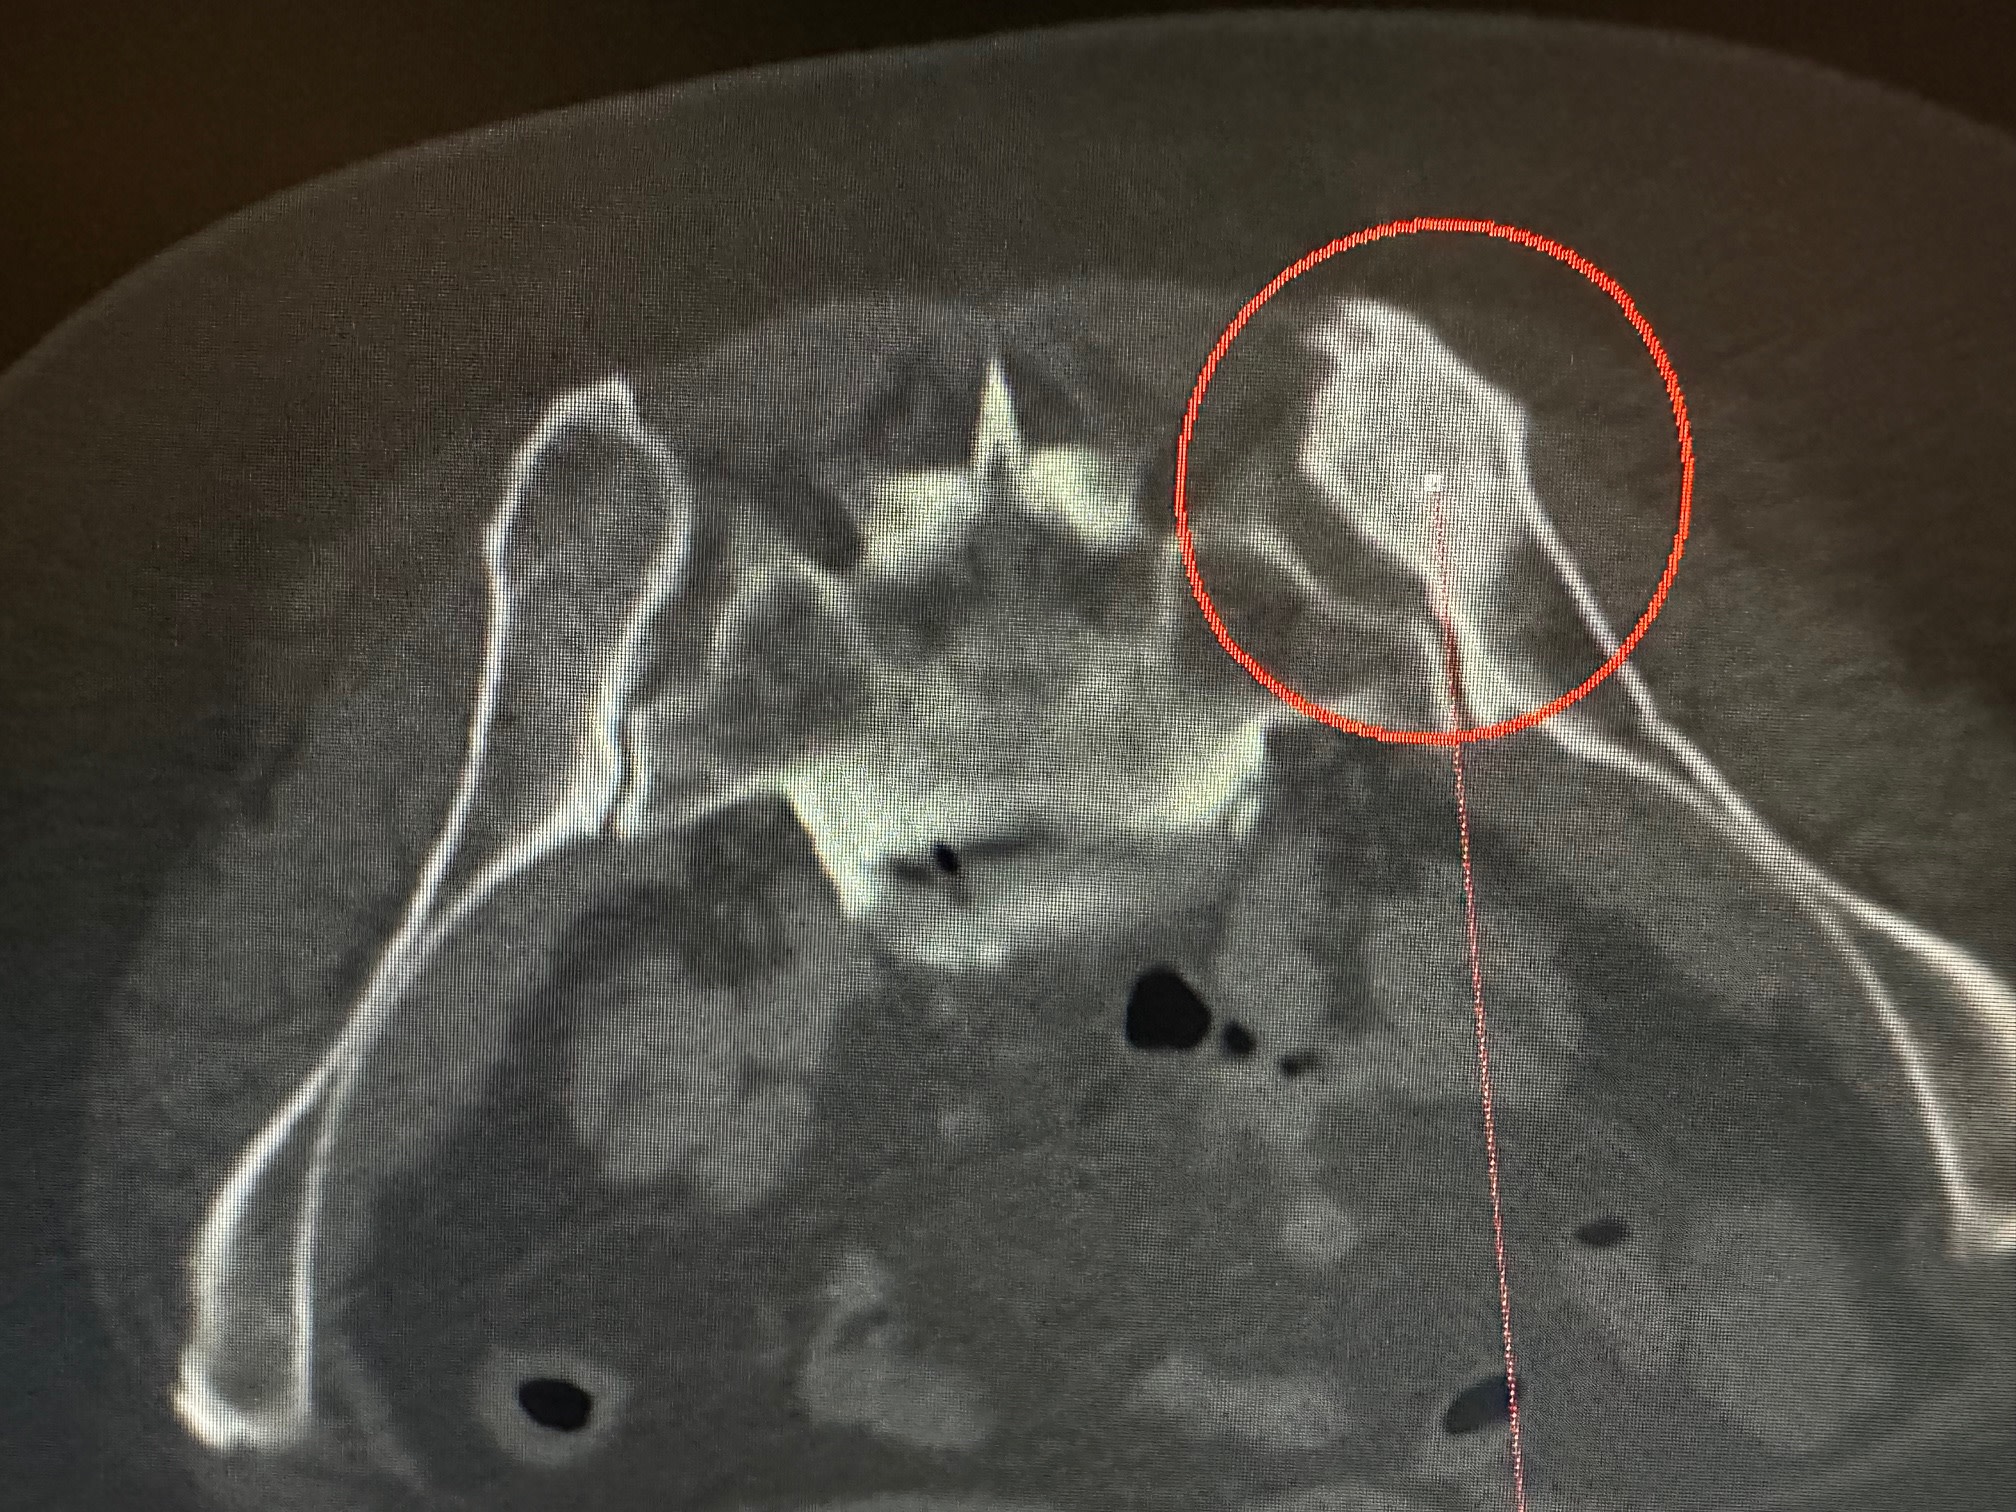

Les interventions, effectuées sous sédation, anesthésie locale ou, plus rarement, anesthésie générale, consistent à insérer des aiguilles dans la tumeur, sans nécessiter d'incision chirurgicale, sous contrôle et guidage précis par scanner dans notre salle dédiée.

À l'extrémité de ces aiguilles, un glaçon se forme, atteignant une température comprise entre -20 et -40°C, entraînant la mort des cellules tumorales.

L'un des principaux avantages de cette technique réside dans sa précision, permettant aux radiologues interventionnels de visualiser en temps réel la formation du glaçon de cryothérapie au sein de la tumeur, assurant ainsi une efficacité optimale de la destruction tout en préservant au maximum les tissus sains environnants.